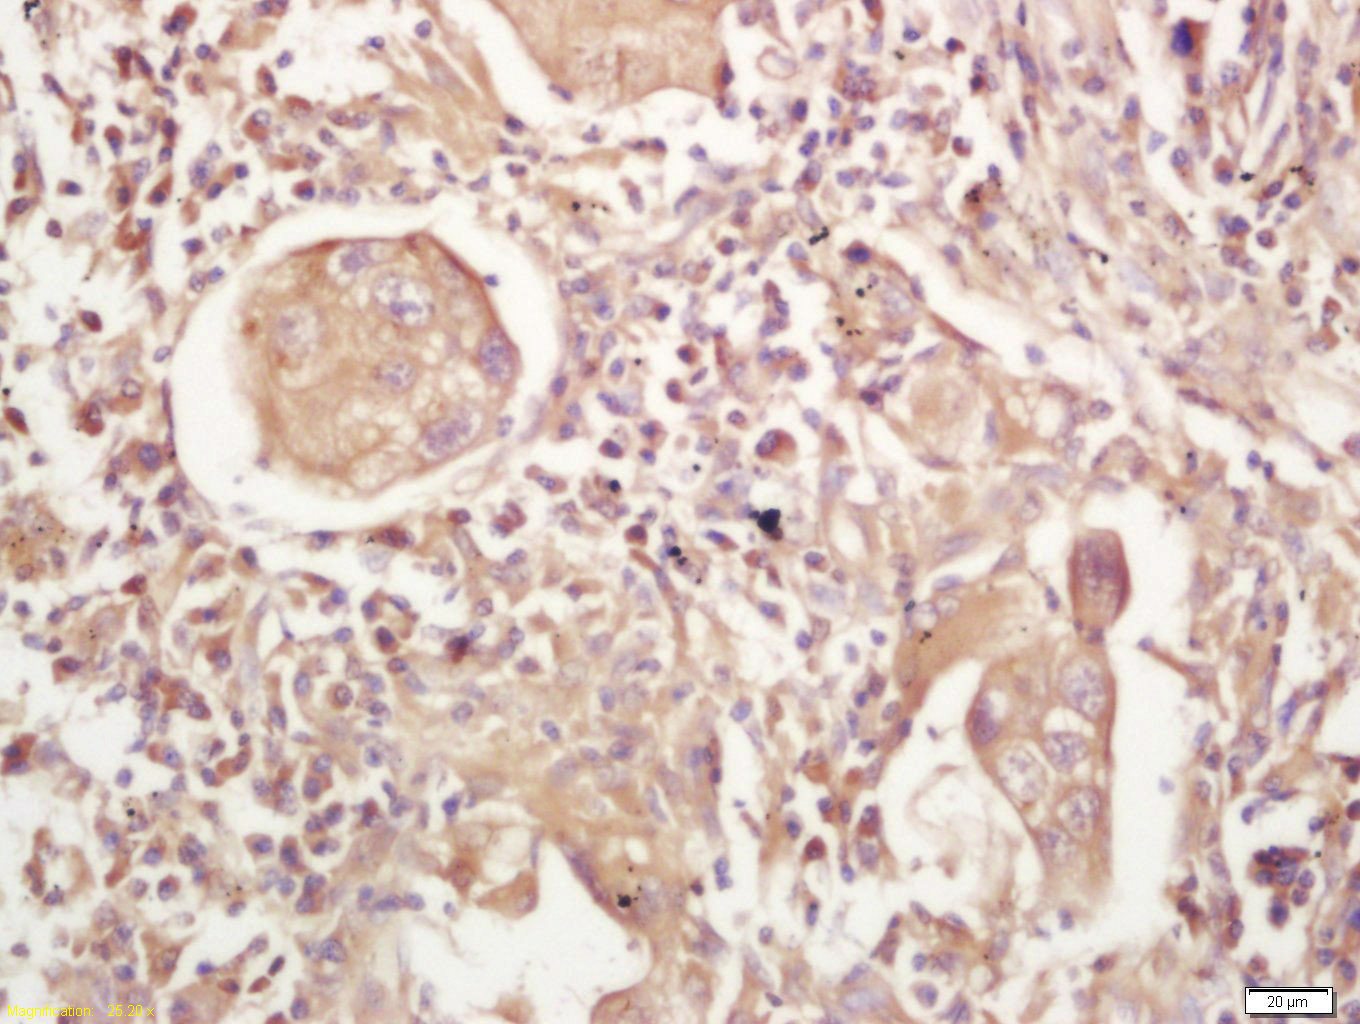

Tissue/cell: human lung carcinoma; 4% Paraformaldehyde-fixed and paraffin-embedded; Antigen retrieval: citrate buffer ( 0.01M, pH 6.0 ), Boiling bathing for 15min; Block endogenous peroxidase by 3% Hydrogen peroxide for 30min; Blocking buffer (normal goat serum,C-0005) at 37℃ for 20 min; Incubation: Anti-MHC Class II Polyclonal Antibody, Unconjugated(bs-8481R) 1:200, overnight at 4°C, followed by conjugation to the secondary antibody(SP-0023) and DAB(C-0010) staining